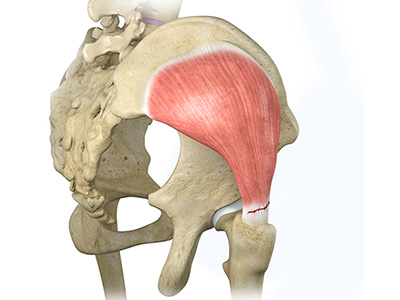

- Gluteals: These are the muscles that form the buttocks. There are three muscles (gluteus minimus, gluteus maximus, and gluteus medius) that attach to the back of the pelvis and insert into the greater trochanter of the femur.

Hip Dislocation Gluteus Tendon Tear

Gluteus Tendon Tear Hip Abductor Tears

Hip Abductor Tears Hamstring Injuries

Hamstring Injuries Gluteus Medius Tear

Gluteus Medius Tear Hip Pain